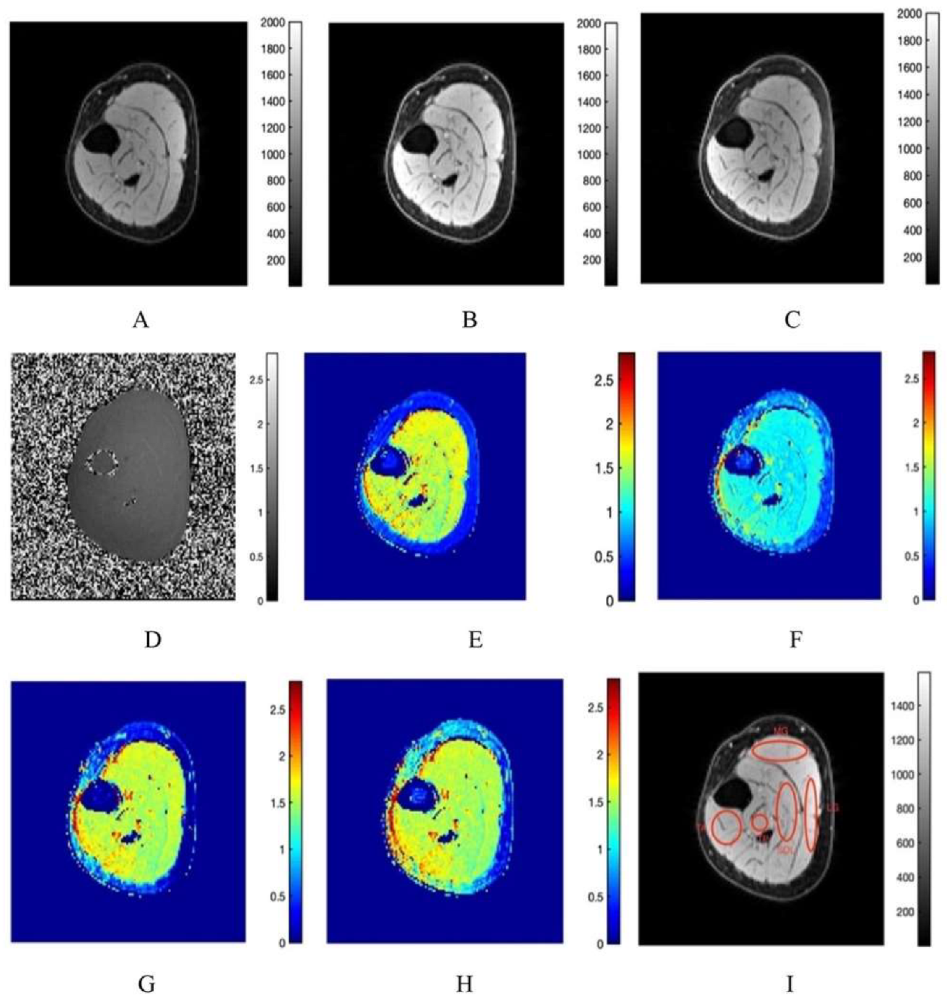

2.3. Computation of T1 and MTsat Maps

3.1. Fat Suppression

3.2. T1 Mapping